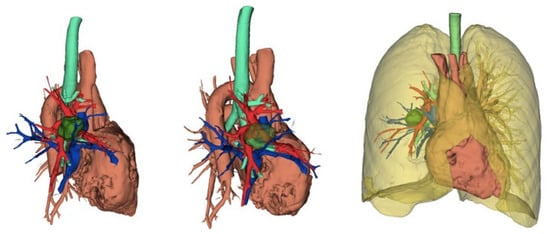

Figure 2. Three-dimensional reconstruction showing the anatomical relationships of the tumor with the thoracic structures.

In the literature, there is still little data concerning robotic pneumonectomies. In 2021, Patton and colleagues described a series of 13 patients who underwent robotic pneumonectomy. Of these, 8 procedures were carried out with a minimally invasive approach, whereas 5 cases were converted to thoracotomy. The average hospital stay for robotic pneumonectomies was 4 days, while for converted cases it was 7 days. The duration of surgery was significantly longer in converted cases (226 min vs. 374). All conversions occurred for anatomical reasons, not because of hemorrhage [31]. In 2021, Scheinerman described an anterior approach to robotic pneumonectomy with the isolation of the inferior pulmonary vein followed by that of the superior pulmonary vein. In left pneumonectomies, it is necessary to perform an extensive lymphadenectomy in order to isolate the main bronchus at the origin and reduce to a minimum the length of the stump [43]. In a recent paper, Louie concluded that robotic pneumonectomy requires further development, particularly in terms of management of the pulmonary artery and of the evaluation of the bronchial stump length on the left. Finally, robotic pneumonectomy should be reserved for centers with considerable experience [44] (Figure 2).

5.2. Role of Advanced Software in Preoperative Planning

Modern planning software has introduced an unprecedented level of accuracy in robotic thoracic surgery. Three-dimensional (3D) reconstruction and virtual simulation software, such as Synapse 3D (version 3.0) and Materialize Mimics (Materialize), facilitate an in-depth understanding of each patient’s unique anatomy. These tools create a 3D model based on preoperative CT or MRI images, which enables surgeons to virtually explore the operative site, plan incisions, and determine the most appropriate pathway for the robotic instruments. This technology is particularly valuable in complex cases involving lung cancer, where a precise understanding of the relationship between the tumor and surrounding vasculature can significantly impact surgical decision-making.